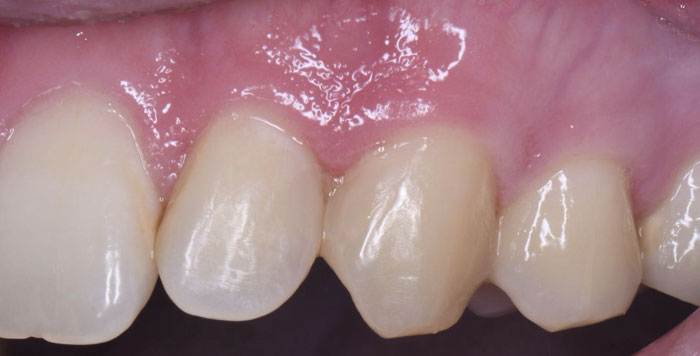

| 主訴 | 欠けた歯を治したい |

| 治療期間 | 1日 |

| 治療費 | ¥22,000 |

| 治療内容 | コンポジットレジンにて修復しました。切端の透明感や亀裂(クラック)を隣の歯と同じように再現できました。患者様には大変満足していただけました。 |

| 治療のリスク | 欠けたり、経年的な変色の可能性があります。 |